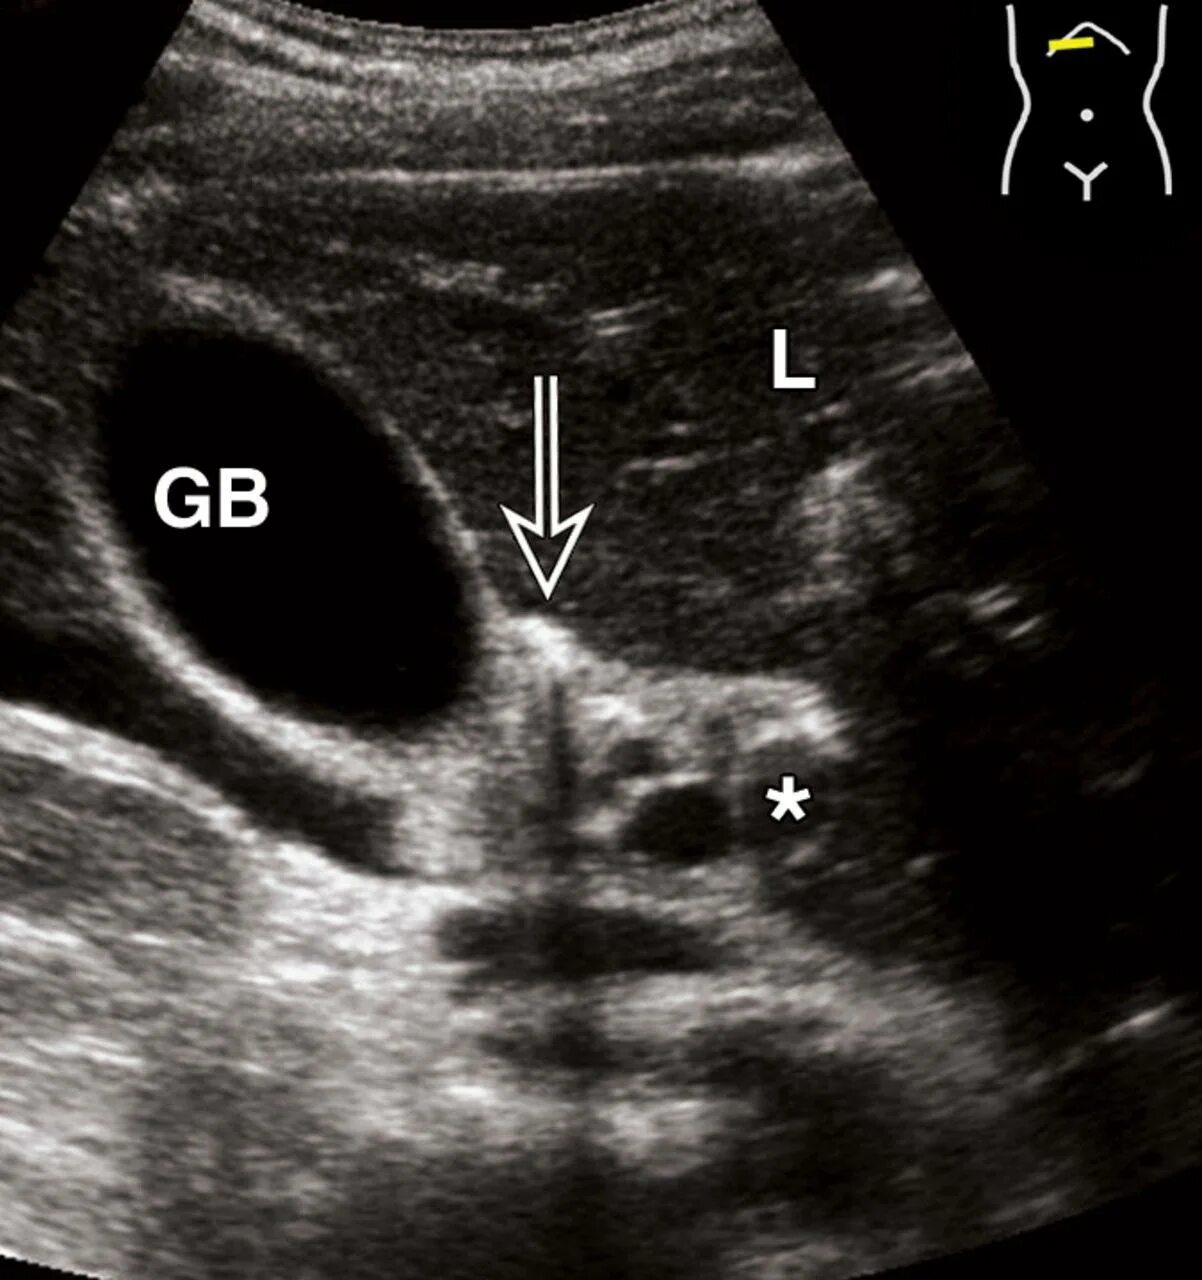

Как выглядит узи живота